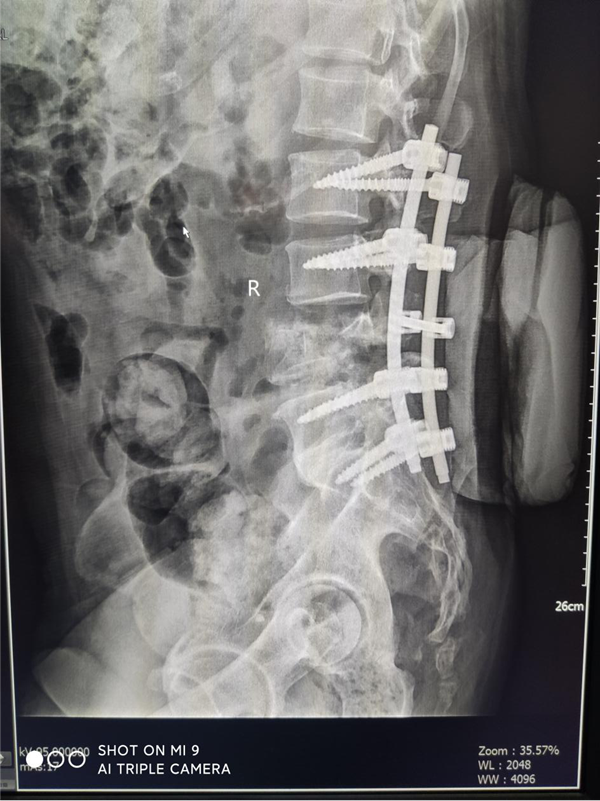

患者刘某,男,55岁,高处坠落致腰部疼痛伴双下肢麻木16小时主诉入院,由于腰部先着地,当时即觉腰部剧烈疼痛伴双下肢麻木和大小便失禁,伤后无昏迷抽搐,无腹痛腹胀,可回忆受伤时情况,伤后未作特殊处理,遂由家属送至我院急诊,查腰椎MRI:腰4椎体爆裂性骨折并继发椎体滑脱,为进一步治疗,急诊收住骨三科。

刘某家属找到了我院骨三科的张纯教授。张教授经过详细了解患者的病情,并判断这是一例严重复杂的脊髓损伤,需要立马进行手术治疗。于是为刘某联系了病房,结合患者年龄大、手术创伤大、出血风险高等特点,经过多次科室讨论及多科室疑难病例会诊,积极联合危重医学科、麻醉科、输血科等相关科室共同制定了周密的手术方案。根据患者病情制定了详细的手术计划及围手术期治疗方案。经过严密的手术前准备,以张纯主任医师为主刀、王伟卓主治医师和黄思华博士为助手,吴刚副主任医师、罗斌医师为麻醉医师,殷敏、马霞为配合护士,黄亚娟、王芳医师为术中诱发电位监护医师的手术团队努力下,手术顺利完成,切开复位内固定保护了严重受伤的脊髓,并进行了脊柱的重建。

患者罗某来院时诊断为腰椎爆裂骨折伴脊髓损伤,腰5椎体和右侧股骨干骨折,双下肢感觉消失,运动功能丧失,术前(ASIA)评级为A级,行腰椎骨折切开复位内固定术及术后康复治疗,一月后(ASIA) 评级恢复到C级。

患者王某来院时诊断为胸腰椎骨折脊髓损伤伴双下肢瘫,胸12/腰1/腰2椎体骨折,数前评级(ASIA)为A级,行胸椎腰椎骨折切开复位钉棒内固定术,一月后(ASIA) 评级恢复到D级,现已转康复科继续治疗。